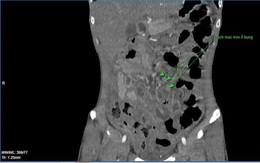

Lao màng bụng, bệnh diễn biến nhanh, dễ tử vong

Đau bụng, chán ăn có thể là biểu hiện của lao màng bụng. Bệnh có thể diễn biến rất nhanh, có thể gây tắc ruột…dễ tử vong.